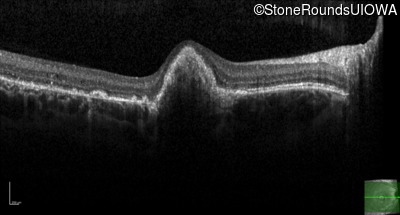

Age at visit: 14 years

This 15 year old girl came to medical attention during a routine athletic vision screening when the acuity in her right eye was observed to be abnormal.